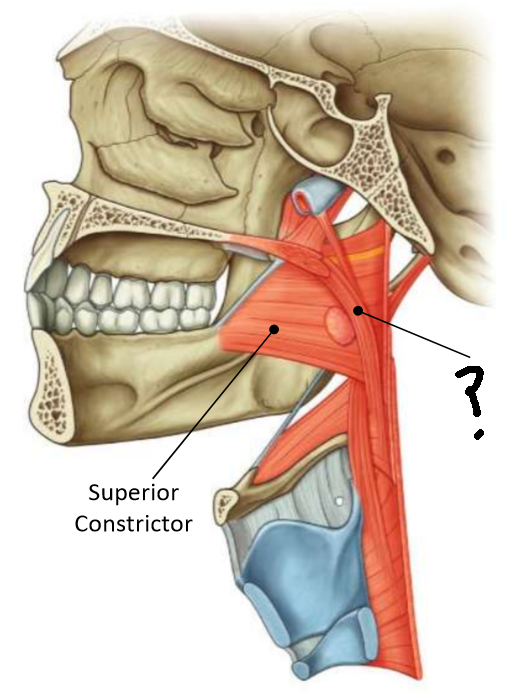

What muscle is this?

superior constrictor

What is the upper border of this muscle?

palatopharyngeal sphincter

What is 1?

pterygomandibular raphe

What is 2?

stylohyoid ligament

What are the attachments of this muscle?

pterygoid hamulus, pterygomandibular raphe, posterior end of mylohyoid line → pharyngeal raphe